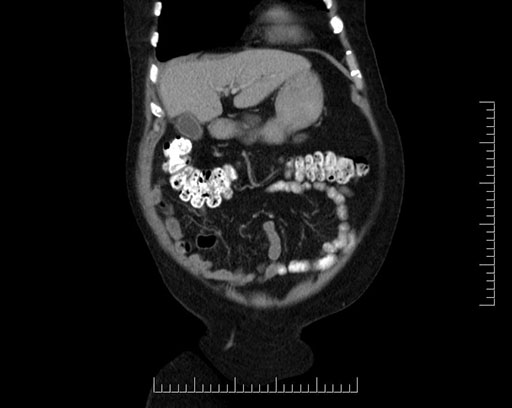

Whipple (pancreaticoduodenectomy) [case 7]

Imaging Analysis

Look through the patient's CT scan to identify any areas of concern for the necessary procedure.

Coronal - stented